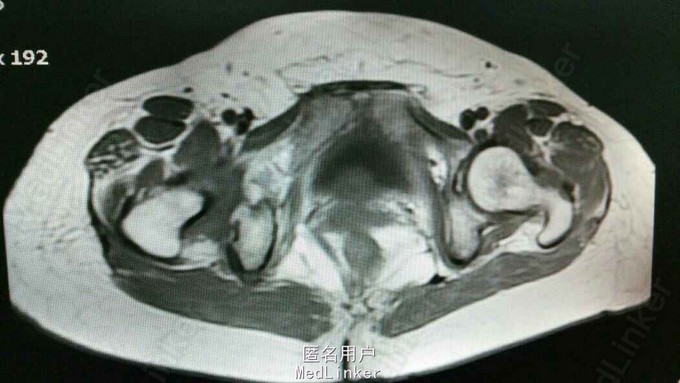

主诉:同房后阴道流血5年。患者,女性,50 岁,G4P2,既往顺产2次,人流2次。既往月经规律,无周期改变,量中。同房后出血,行诊刮术,病理提示子宫癌肉瘤。

查体:外阴正常,阴道通畅,宫颈3度糜烂,接触性出血,子宫增大如孕9周,均匀增大。行MRI检查结果如下:

诊断:子宫癌肉瘤,行腹腔镜下子宫切除,双侧附件切除,盆腔淋巴结清扫,腹主动脉旁淋巴结清扫,大网膜切除。术程顺利。